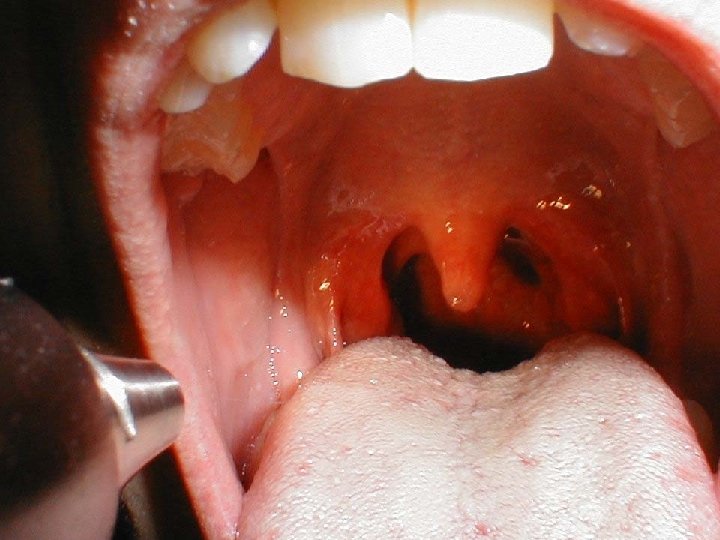

Pharyngitis Clinical Presentation • Clinical presentation with soreness of the throat, may be dysphagia and pain on swallowing, fever and additional upper respiratory symptoms may also be present, Tender cervical lymphadenopathy

Pharyngitis-Clinical Presentation • Exudative or Diffuse erythema-Group A , C, G Streptococcus , EBV, Neisseriae gonococcus C. diphtheriae, A. haemolyticum, Mycoplasma pneumoniae • Vesicular, ulcerative- Coxsackie A 9, B 1 -5, , ECHO, Enterovirus 71, Herpes simplex 1 and 2 • Membranous- Corynebacterium diphtheriae or Vincent Angina ( anaerobes/spirochetes)

Quinsy Clinical Presentation • Tonsillar Abscess with pain, fever, difficulty swallowing • Drainage of Abscess and antimicrobial therapy